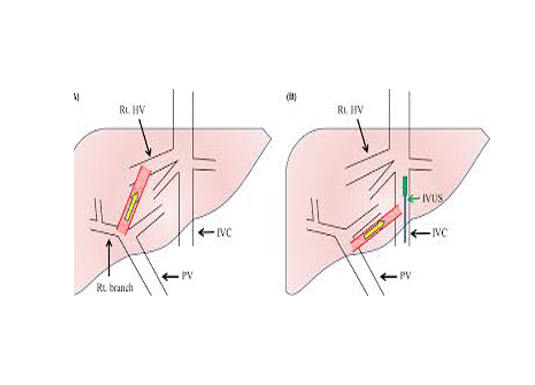

Few patients who need a liver or a renal biopsy have a greater tendency for bleeding complications. In such patients the biopsy is performed from the endovascular side, so that, if at all bleeding happens it is into the blood vessel itself and not out side.